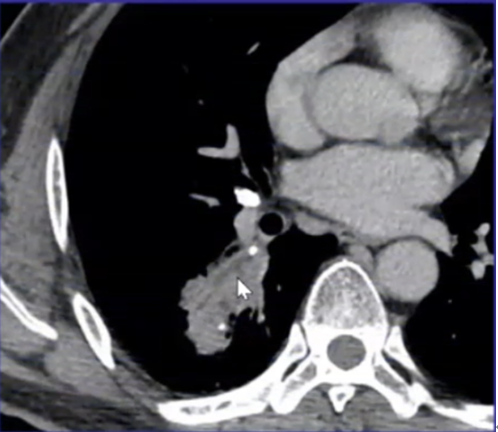

下图为一肿块,周围有晕征,中间有小气泡,增强扫描可见大片坏死,没有强化(图19),这种特征非常像曲霉感染,但最终穿刺病理证实为毛霉感染。其破坏范围更广。临床上,在诊断不清的情况下,一定要做增强扫描,能够帮助确定组织强化的程度。患者出现了胸腔积液,其中的小气泡更大,这是毛霉的特征。

图片

图19  毛霉感染